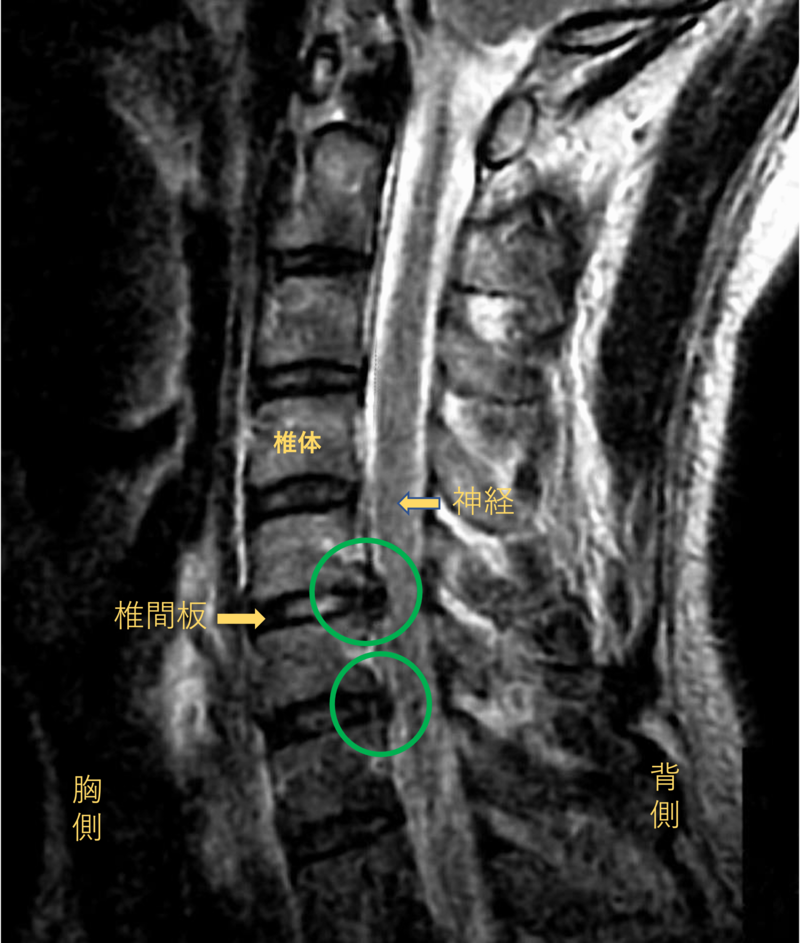

首を横から見たMRI画像です。

頚椎という骨と骨の間に椎間板と呼ばれるクッションがあります。

このクッションの中身が飛び出す状態が椎間板ヘルニアと呼ばれます。

このMRI画像では、椎間板が背中側に飛び出して神経が圧迫されることが痛み、しびれの原因となっておりました。